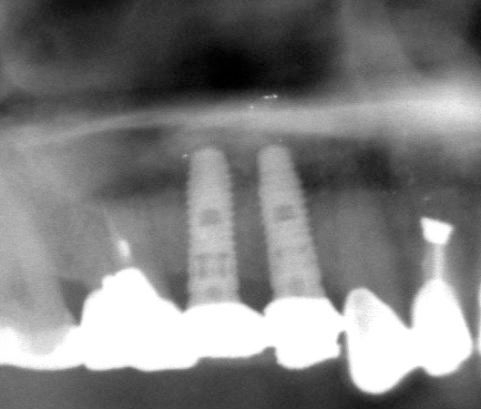

両側5歯症例

両側5歯症例両側5歯症例両側5歯症例 主訴-義歯のバネが壊れて手前の歯が痛んできた。 術前(旧義歯装着、鏡像) 術前(下顎粘膜面、鏡像)術前(下顎粘膜面、鏡像)術前(下顎粘膜面、鏡像) 術前レントゲン術前レントゲン術前レントゲン 術前口腔内(正面観)術前口腔内(正面観)術前口腔内(正面観)

術後(鏡像)術後(鏡像)術後(鏡像) 術後口腔内(正面観)術後口腔内(正面観)術後口腔内(正面観)もう入れ歯は要らなくなりました。 術後レントゲン術後レントゲン術後レントゲン